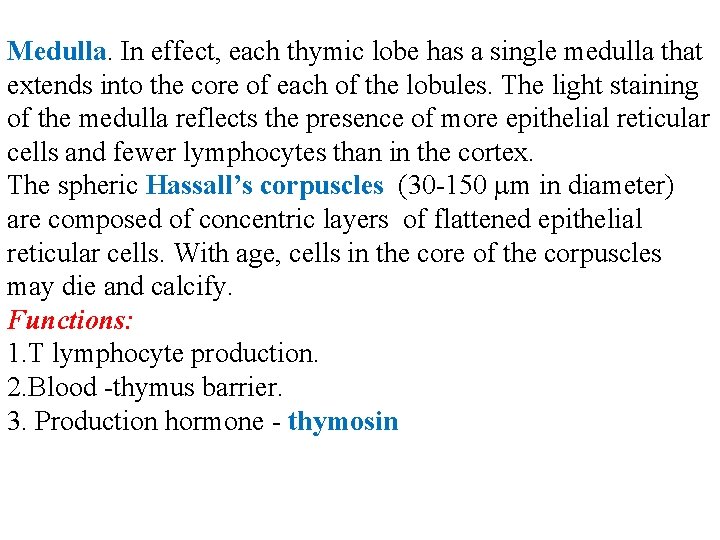

Medulla. In effect, each thymic lobe has a single medulla that extends into the core of each of the lobules. The light staining of the medulla reflects the presence of more epithelial reticular cells and fewer lymphocytes than in the cortex. The spheric Hassall’s corpuscles (30 -150 m in diameter) are composed of concentric layers of flattened epithelial reticular cells. With age, cells in the core of the corpuscles may die and calcify. Functions: 1. T lymphocyte production. 2. Blood -thymus barrier. 3. Production hormone - thymosin